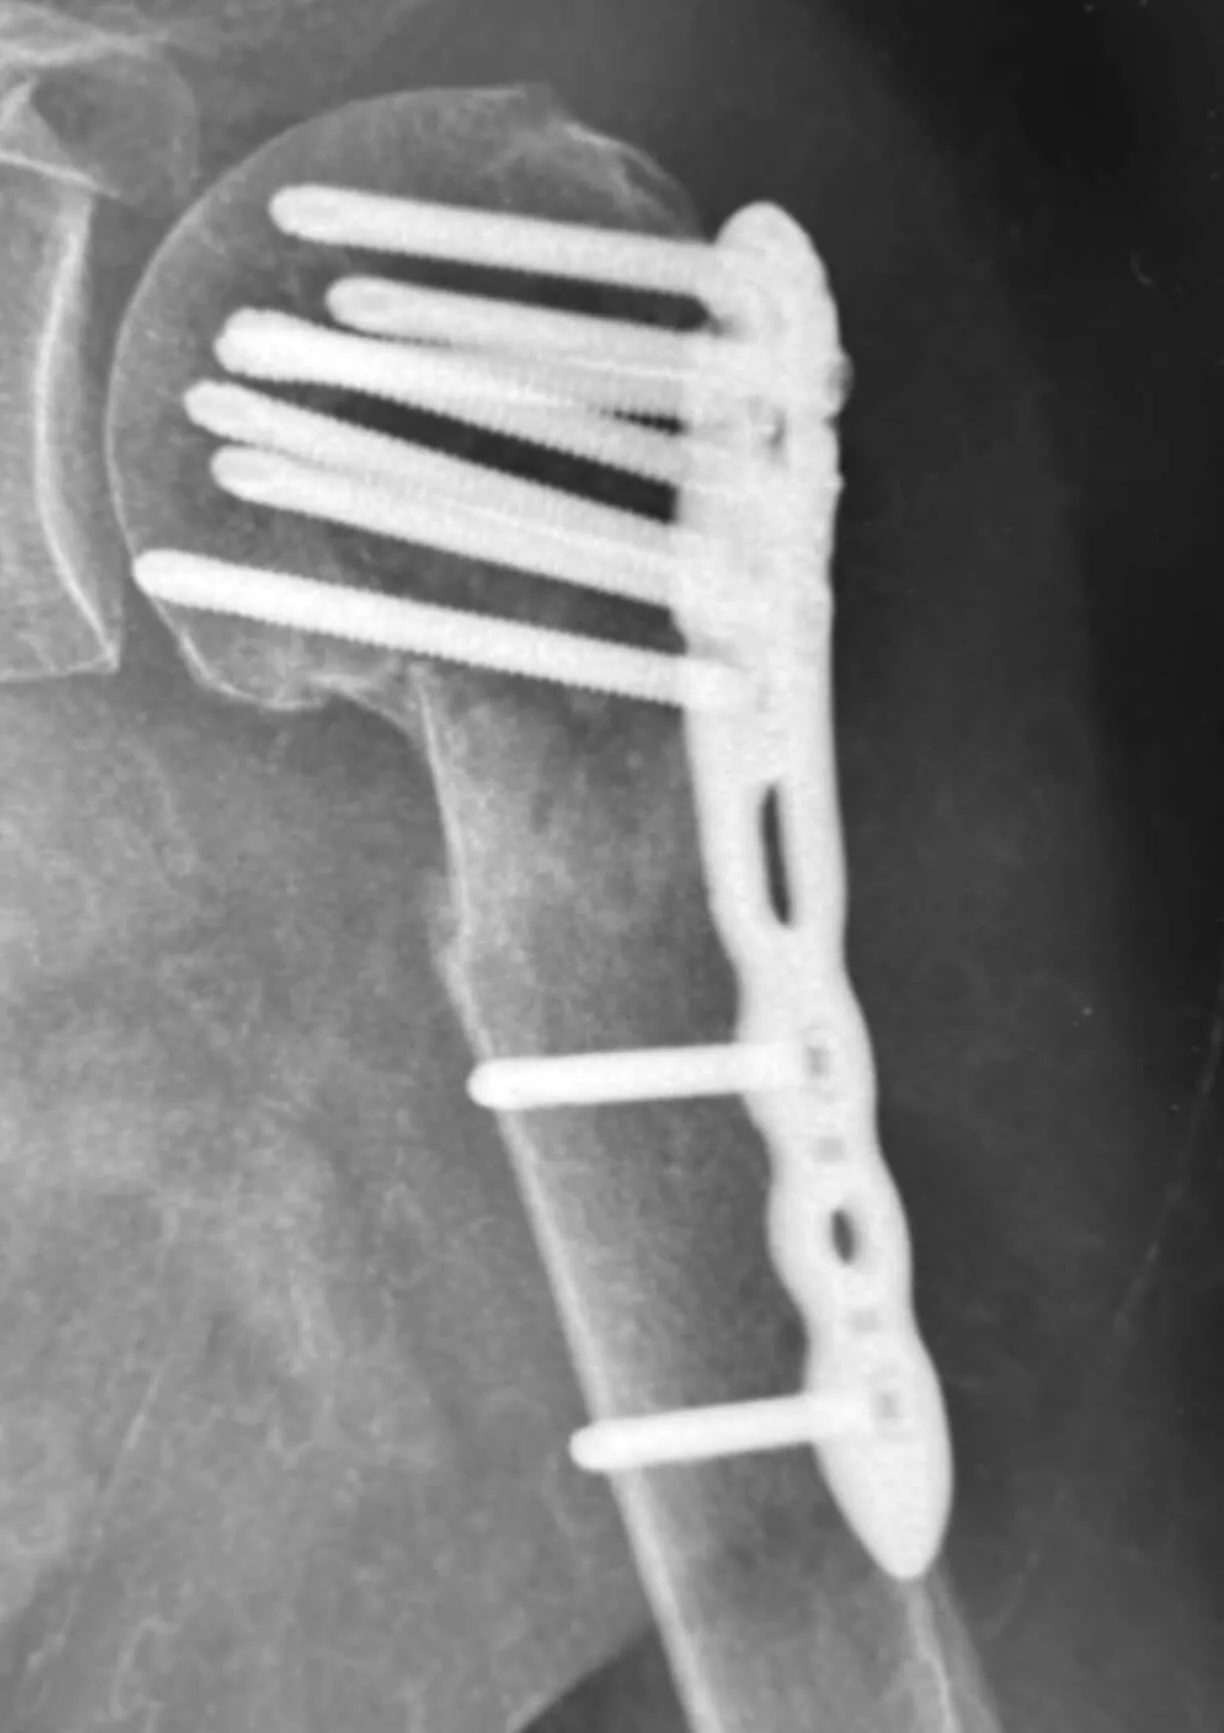

Operacja

Bezpośrednio po operacji

Złamanie bliższego końca kości ramiennej

Pacjentka, lat 76, doznała złamania w wyniku upadku z wysokości własnej. Złamanie miało charakter wieloodłamowy ze znacznym przemieszczeniem kątowym odłamów. Bez leczenia operacyjnego chora nie odzyskałaby dobrego zakresu ruchomości i siły mięśniowej.

Wykonano operację polegającą na otwartym nastawieniu złamania z prawidłowym ustawieniem odłamów kostnych oraz zespoleniem za pomocą płyty ze stabilnością kątową śrub. Dodatkowo przeprowadzono rekonstrukcję uszkodzonego aparatu więzadłowego barku i włączono pooperacyjną rehabilitację.

Pacjentka po 4 miesiącach odzyskała prawidłowy zakres ruchomości, siłę mięśniową oraz pełną funkcję kończyny.